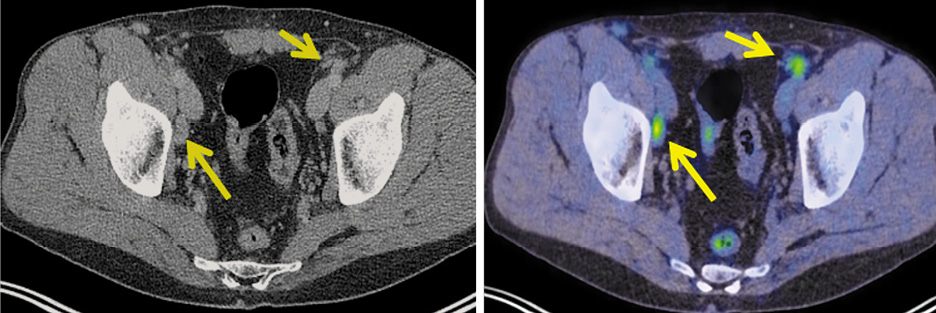

Кроме того, выявлены увеличенные общие, внутренние и наружные подвздошные, а также паховые лимфатические узлы слева, размером до 12 мм, SUVmax 3,91 (рис. 2).

Рис. 2. Больной С., 43 года. На аксиальной КТ- и совмещенной ПЭТ/КТ-проекциях определяются увеличенные лимфатические узлы: общие, наружные и внутренние подвздошные, паховые слева, размером до 12 мм, с повышенной фиксацией радиофармпрепарата, SUVmax 3,91.